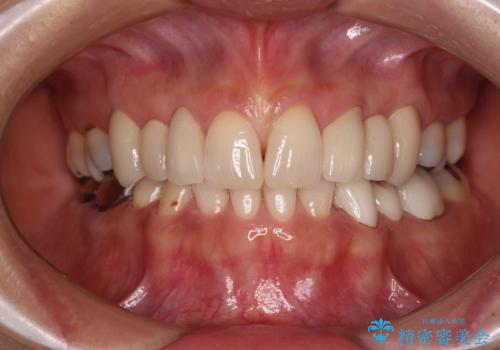

欠損の多い歯列 部分矯正とセラミックブリッジで自然な見た目に

隙間が全て閉じたことで、長年食事の度に挟まる不快感が改善されました。

また、正面から見た印象がまるで自分の歯であるような自然な仕上がりとなりました。